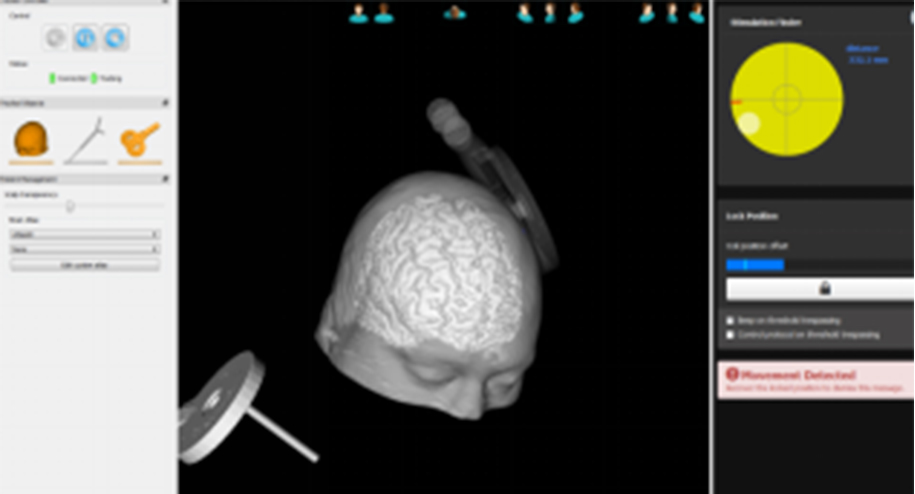

Yingchi TMS 3D navigation system adopts high-precision infrared optical capture technology, which can track and locate the transcranial magnetic stimulation coil with millimeter-level accuracy, and visualize the stimulation focus magnetic field on the anatomical image of the personalized brain. The positioning of the navigation system is intuitive and easy to use, which will help you quickly and successfully complete the key operations of TMS target positioning, thereby greatly improving the effect and efficiency of magnetic stimulation.

Present of the Stimulus Target in 3D

Visualization of stimulus target, support color page in 3D scene to display stimulation target area, in order to highlight it to distinguish it from other brain areas.

Off-target Warning

The navigation system can display and record the three-dimensional coordinates of the stimulation coil, the distance from the cerebral cortex, the angle of the coil, etc. When the stimulation coil deviates from the preset stimulation target, the system will give an early warning through a pop-up window and sound.